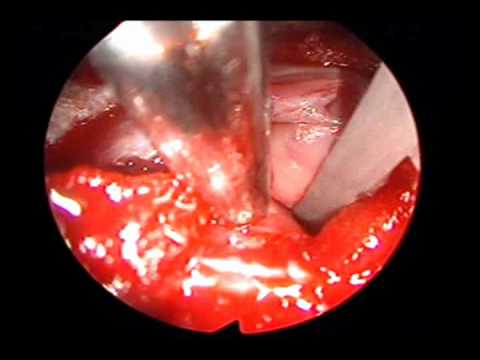

Przednia foraminotomia szyjna

Na filmie doktor Pakzaban prezentuje przednią foraminotomię szyjną z użyciem Bone Scalpel.